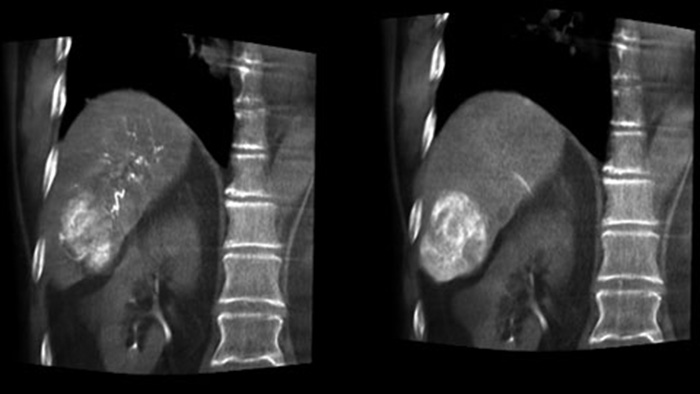

Die Erfassung eines 3D-Bildes nach der Embolisation ermöglicht die Darstellung von gezielt eingebrachtem embolischem Material wie Lipiodol oder röntgenpositiven Partikeln im Tumor.5

Dual View ermöglicht die gleichzeitige Darstellung eines 3D-Bildes der arteriellen Phase vor der Embolisation und eines Bildes nach der Embolisation zur Bestimmung des Behandlungsendpunkts.